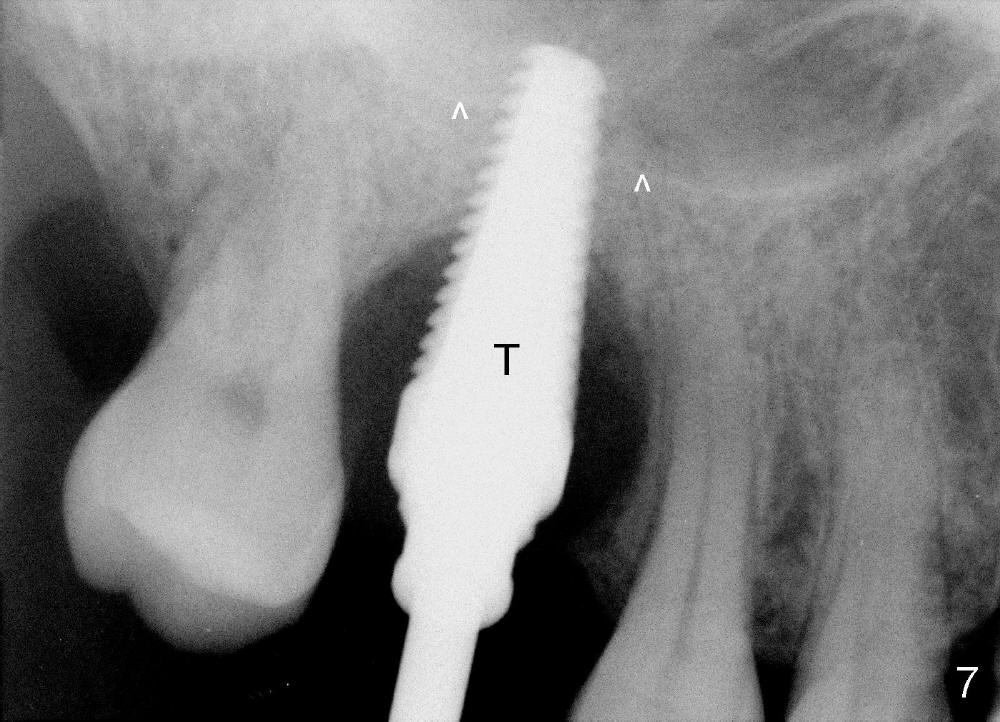

The upper right 1st molar of a 48-year-old man has severe perio endo disease (Fig.1 #3); the bone height for immediate implant (Fig.2) is about 3.5 mm (Fig.1 vertical line). There is a buccal (Fig.3 B) abscess (*); the palatal (Fig.4 P) root is exposed. After extraction, the socket available for immediate implant (Fig.5,6 S) is buccal (without septum), whereas the apex of the palatal root is far away from the main socket. In fact there is an advantage: the socket is smaller. Osteotomy is created in the main socket as palatal as possible, using osteotomes, reamers and taps (Fig.7 T). The sinus floor is lifted (Fig.7 ^). When 7x17 mm implant is placed (Fig.8 I), the insertion torque is >60 Ncm. The remaining socket (Fig.8 *) is to be packed with mixture of autogenous bone, allograft and synthetic bone (Osteogen) (Fig.9,10 <). Immediate insertion of an abutment (Fig.8-10 A) helps retain perio dressing (Fig.11,12). No collagen membrane is used in this case to cover the bone graft before placement of perio dressing. Postop the patient cannot tolerate oral Amoxicillin because of stomach upset. The dose is reduced. Two weeks postop, the perio dressing is stable, but discolors (Fig.13). When the dressing is removed, the buccal bone graft is exposed, which is not abnormal. What is unusual is discoloration (Fig.14). The significance of the latter is not revealed until 3 months postop when the patient remains asymptomatic, but there is an apical fistula (Fig.15 <). There is a communication between the fistula and the buccal sulcus of the implant: water passing freely. Based on the position of the buccal plate of the neighboring teeth (*), the buccal plate of the implant should be lost, which is consistent with finding of PA (Fig.16, as compared to Fig.8). Guided bone regeneration seems necessary.